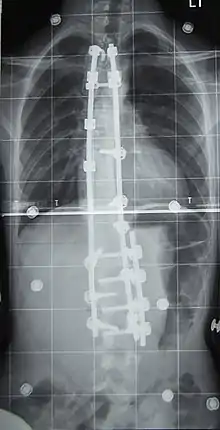

Surgery is usually recommended by orthopedists for curves with a high likelihood of progression (i.e., greater than 45–50° of magnitude), curves that would be cosmetically unacceptable as an adult, curves in people with spina bifida and cerebral palsy that interfere with sitting and care, and curves that affect physiological functions such as breathing.[101][102]

Surgeons who are specialized in spine surgery perform surgery for scoliosis. To completely straighten a scoliotic spine is usually impossible, but for the most part, significant corrections are achieved.[104]

The two main types of surgery are:[105]

- Anterior fusion: This surgical approach is through an incision at the side of the chest wall.

- Posterior fusion: This surgical approach is through an incision on the back and involves the use of metal instrumentation to correct the curve.

One or both of these surgical procedures may be needed. The surgery may be done in one or two stages and, on average, takes four to eight hours.